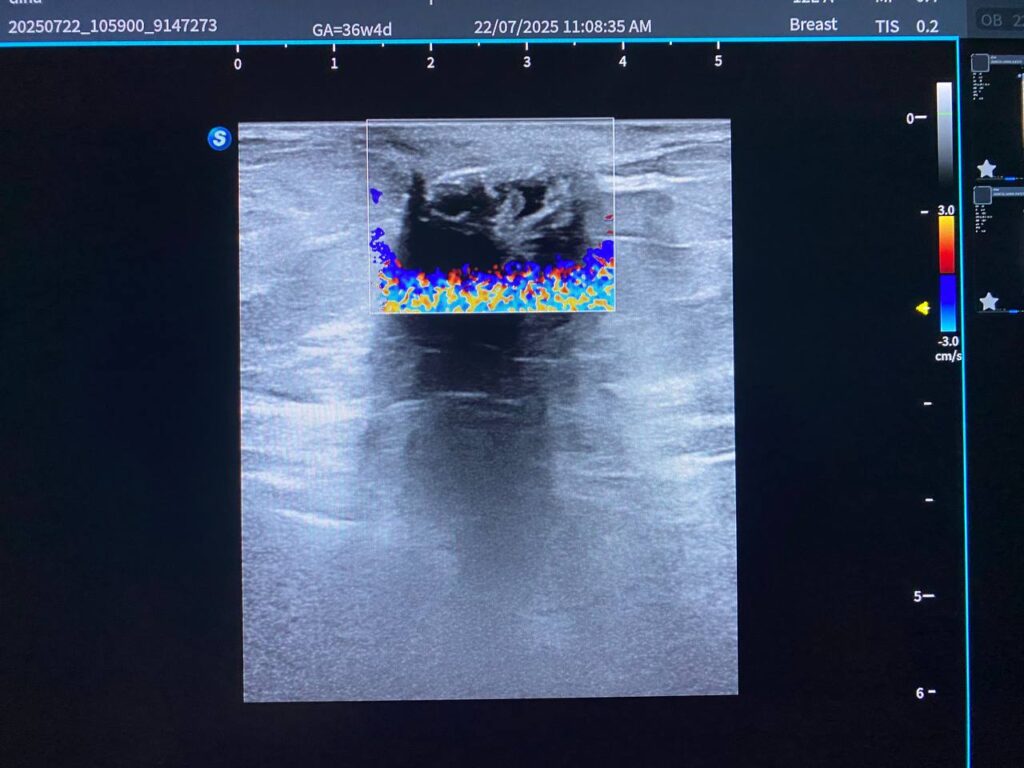

Findings: Left breast: UOQ ,scar tissue+ presence of heterogenous calcified mass 5.3×8.1mm, under the skin , mostly calcified hematoma ,no suspicious solid mass, nor collection seen at the bed, nor at the other part of the breast

Findings: Left breast: UOQ ,scar tissue+ presence of heterogenous calcified mass 5.3×8.1mm, under the skin , mostly calcified hematoma ,no suspicious solid mass, nor collection seen at the bed, nor at the other part of the breast